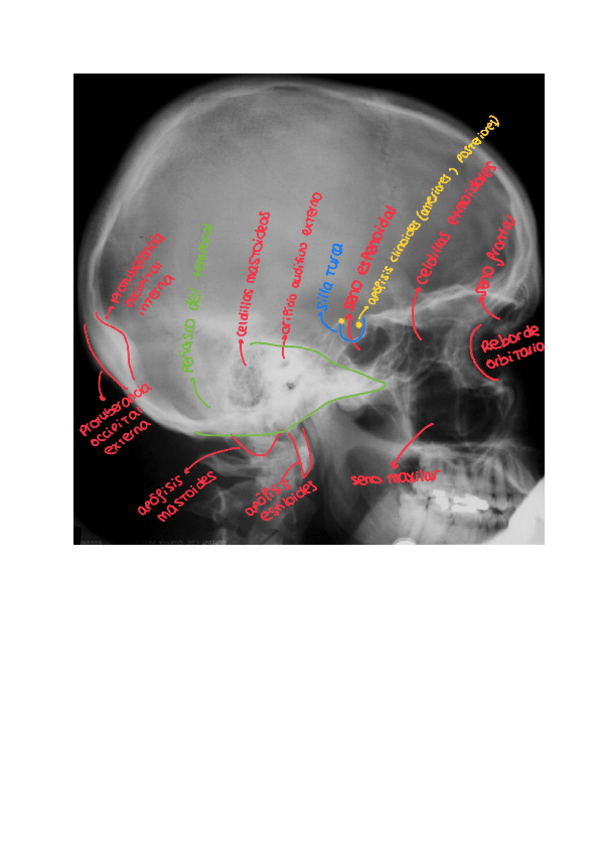

Otros - CRANEO-Esquemas-con-Dibujos.pdf

8 páginas